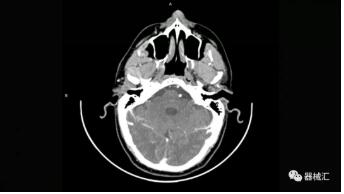

▲ SOMATOM On.site圖像